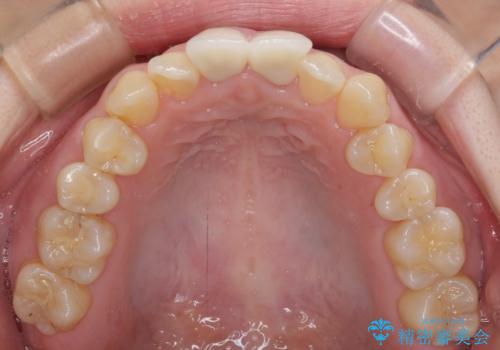

変色した前歯のオールセラミック治療

- 前歯の変色が気になるとのことで来院された患者様です。

レントゲン写真より、変色してしまった歯は根管治療がされていなかったため、根管治療後にファイバーコアによる土台築製を行い、前歯2本をオールセラミッククラウンにて補綴することとしました。

変色とともに、捻れていたことも気になっていたので、その両方を解決させることとしました。

2本同時に処置したことで、形や色調をそろえることができ、自然な口元になりました。